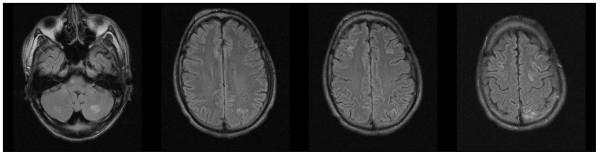

A 21-year-old Caucasian man with Goodpasture's disease and end-stage renal disease presented with two generalized seizures after a period of mild cognitive disturbance. Blood pressure and routine laboratory tests did not exceed the patient's usual values, and examination of cerebrospinal fluid was unremarkable. Cerebral magnetic resonance imaging (MRI) revealed multiple cortical and subcortical lesions on fluid-attenuated inversion recovery sequences. Since antiglomerular basement membrane antibodies were found to be positive with high titers, plasmapheresis was started. In addition, cyclophosphamide pulse therapy was given on day 13. Encephalopathy and MRI lesions disappeared during this therapy, and antiglomerular basement membrane antibodies were significantly reduced. Previous immunosuppressive therapy was performed without corticosteroids and terminated early after 3 months. The differential diagnostic considerations were cerebral vasculitis and posterior reversible encephalopathy syndrome. Vasculitis could be seen as an extrarenal manifestation of the underlying disease. Posterior reversible encephalopathy syndrome, on the other hand, can be triggered by immunosuppressive therapy and may appear without a hypertensive crisis.

一名21岁患有古德帕斯丘病和终末期肾病的白种男性,在经历一段轻度认知障碍后出现两次全身性癫痫发作。血压和常规实验室检查未超过患者的通常值,脑脊液检查无异常。脑部磁共振成像(MRI)在液体衰减反转恢复序列上显示多个皮质和皮质下病变。由于发现抗肾小球基底膜抗体高滴度阳性,遂开始进行血浆置换。此外,在第13天给予环磷酰胺脉冲治疗。在此治疗期间,脑病和MRI病变消失,抗肾小球基底膜抗体显著降低。先前的免疫抑制治疗未使用皮质类固醇,3个月后提前终止。鉴别诊断考虑为脑血管炎和后部可逆性脑病综合征。血管炎可视为潜在疾病的肾外表现。另一方面,后部可逆性脑病综合征可由免疫抑制治疗引发,且可能在无高血压危象的情况下出现。